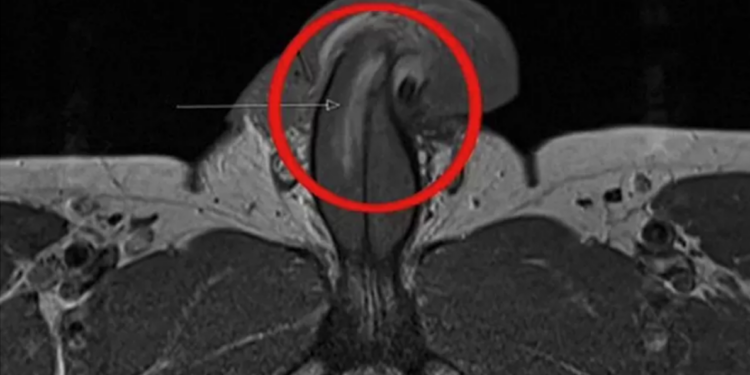

No entanto, no caso do homem cujo pênis foi fraturado verticalmente, os médicos disseram que ele não relatou nenhuma sensação de estalo, perda gradual da ereção ou inchaço moderado. Após uma ressonância magnética, um cirurgião confirmou que ele sofreu uma ruptura vertical de três centímetros no pênis.